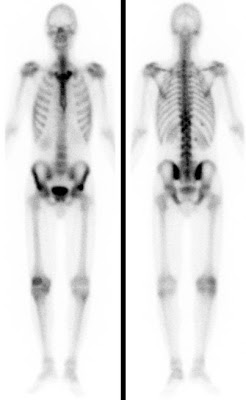

Bei der Skelettszintigraphie werden schwach radioaktiv markierte Phosphatkomplexe verabreicht, die zunächst im Blut durch den Körper zirkulieren und im Verlauf von 2-3 Stunden ausreichend in den Knochen eingebaut werden, so dass dann der Knochenstoffwechsel abgebildet werden kann.

Es bestehen die Möglichkeiten, gleich nach Verabreichung der Phosphatkomplexe die Durchblutung zu untersuchen und auf den Spätaufnahmen den Knochenumbau zu beurteilen. Bei der Skelettszintigraphie gibt es keine Unverträglichkeitsreaktionen auf die verabreichten Radiopharmaka. Im Gegensatz zu vielen Röntgenkontrastmitteln sind die verwendeten Radiopharmaka auch nicht nierenschädlich.

Die Hauptfragestellungen bei der Skelettszintigraphie betreffen die Feststellung evtl. Knochenmetastasen bei Krebserkrankungen und die Unterscheidung von primär entzündlichen vs. primär degenerativen Gelenkerkrankungen, also rheumatischen Grunderkrankungen mit Skelettbeteiligung vs. (aktivierten) Arthrosen.

Darüber hinaus ist die Skelettszintigraphie häufig auch bei der Abklärung unklarer Knochenschmerzen sehr hilfreich, etwa zur Feststellung evtl. Knochentumoren, von Prothesenlockerungen, einer Osteomyelitis, von Frakturen, von Knocheninfarkten etc.